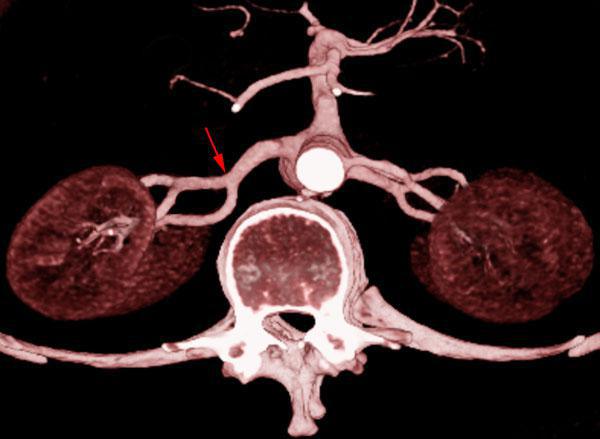

Arteria renal torácica